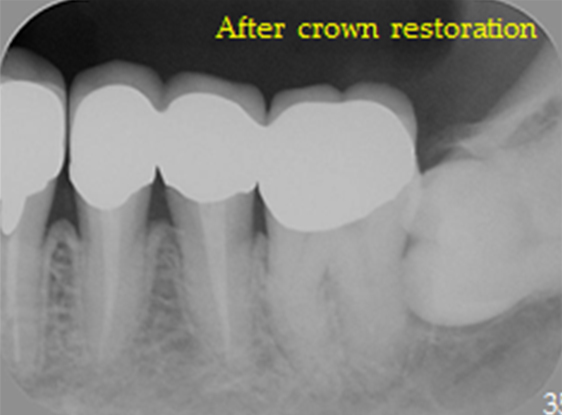

| 治療法 | 矯正治療 自家歯牙移植 メタルボンドセラミッククラウン |

治療前-治療後